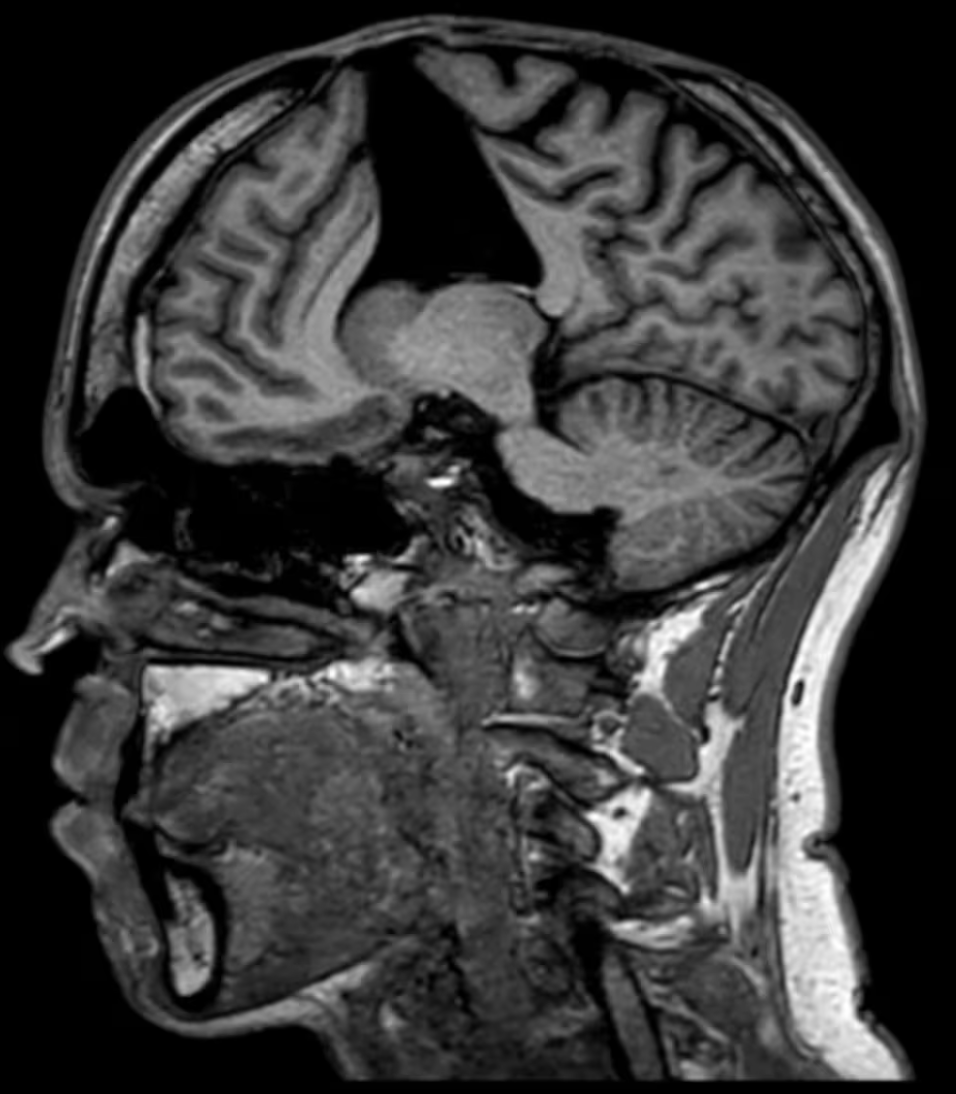

家人带他到医院,经过一系列检查后,医生在他大脑里发现了关键线索:脑部影像提示,他可能患有脑淀粉样血管病(CAA)。

这是一种脑血管疾病,主要是因为一种叫做“β-淀粉样蛋白”的物质在大脑血管壁上异常沉积,导致血管变得脆弱,容易破裂出血,也会引起逐渐加重的认知功能下降——症状表现很像阿尔茨海默病。

医生们开始翻阅他的病史,终于追溯到他在婴儿时期的那次硬脑膜移植手术,并得出了诊断——医源性脑淀粉样血管病(iCAA)。